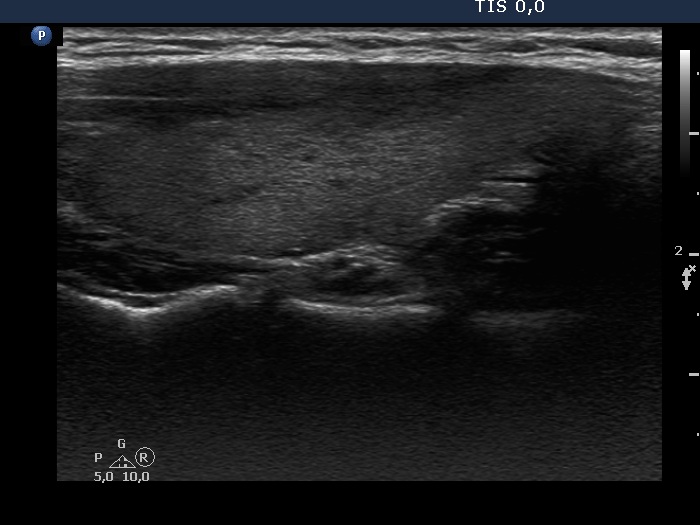

Consecutive patients with the final diagnosis of Hashimoto's thyroiditis - case 54 (767) (ultrasonographic picture 6)

Left lobe, another longitudinal view. The moderately hypoechogenic area is demonstrated in another section.